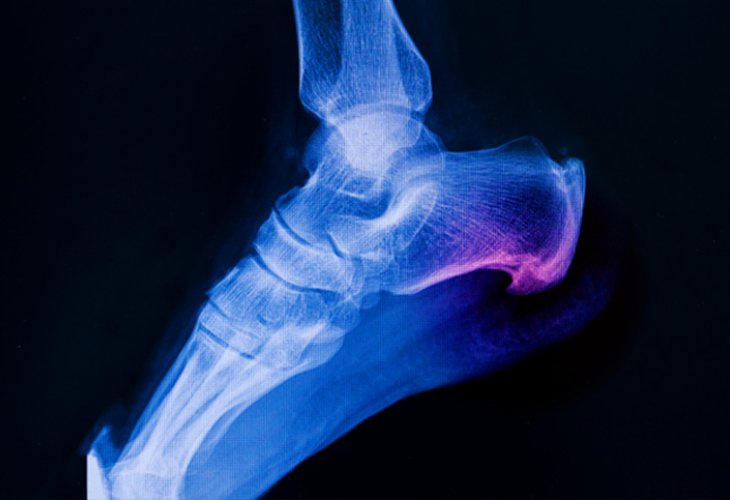

(Photo: shutterstock)The condition known as plantar fasciitis is one of the most common foot ailments. It involves inflammation of the thick tissue at the bottom of the foot, connecting the heel bone to the toes. This inflammation can cause severe pain and often disrupt daily activities.